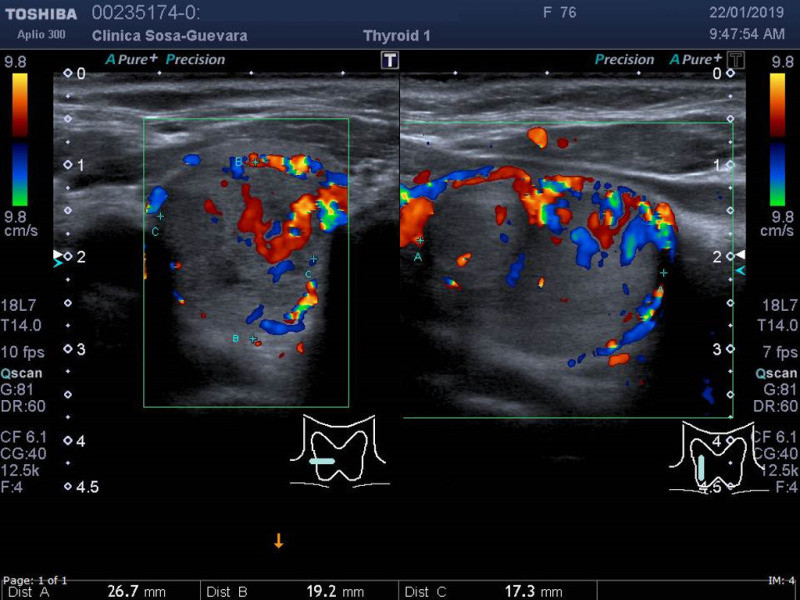

Ultrasonido de tiroides

Envíado por Clínica de Radiología y Ultrasonografía Sosa - Guevara